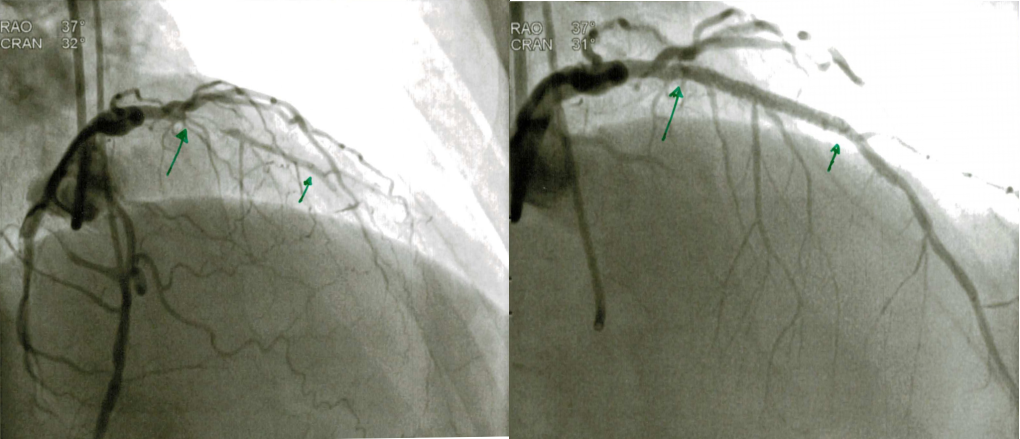

Mit hjerte før og efterPå det billedet til venstre, Ved den venstre grønne fil, kan man se en lille hårtynd streg. Her havde både den første kirug og CT scanningen konstateret at der var helt tillukket. På billedet til højre er der åbnet og indsat en stent.